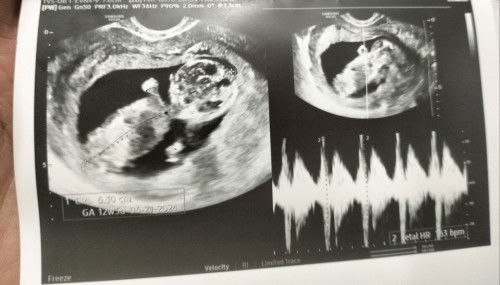

Naka 3x PT nko pero negative naman. 2 weeks nkong delayed pero nagtetake ako ng pills diane 35 ang gamit ko regular naman ako pero bat ganun hindi parin ako nagkaka roon normal lang ba yun sa nagpipills? First time mom po ako. Pahelp naman po. Tia :) #pt #firsttimemom #dianepills #contraceptivepills